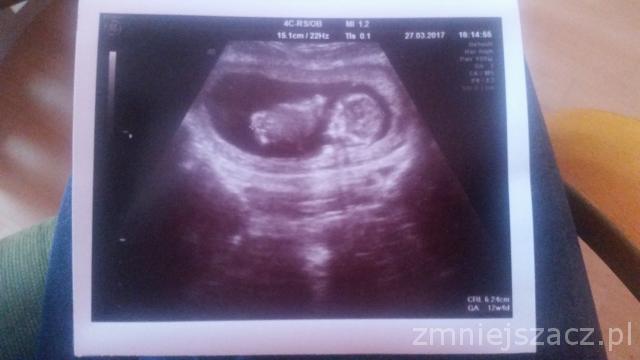

Ja wrzucam zdjęcie mojego chłopca :) zdziwiłam się bo z usg wychodzi 6,2 cm i 12t4dzien, a dokładnie 4 tygodnie temu miał 8t0d wiec strasznie szybko rośnie :) Zobacz załącznik 800455